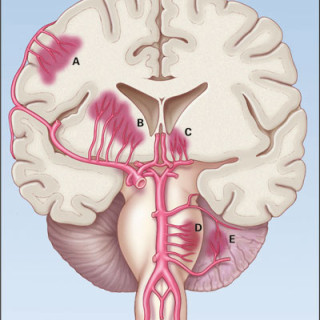

Den første detaljerte beskrivelsen av cerebral venetrombose, også kalt sinusvenetrombose, ble forfattet av Ribes i en artikkel fra 1825 (1). Siden fulgte en rekke kasuistikker basert på autopsimaterialer, som førte til den oppfatning at cerebral venetrombose representerte en sjelden, alvorlig sykdom karakterisert med hodepine, papillødem, epileptiske anfall, fokale utfall, progredierende koma og død (2, 3). Introduksjon av moderne nevroradiologisk utredning har gjort diagnostisering intra vitam mulig, dermed er det blitt klart at sykdomsutviklingen ved cerebral venetrombose heller sjelden er i...